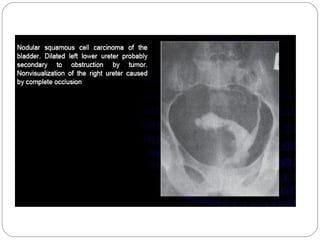

Bladder

By 15–30 minutes after the injection of contrast

material, the bladder is often sufficiently filled, and the

15-minute KUB radiograph may be adequate for

evaluation.

 As the bladder distends with contrast the intraluminal

contrast material should be spheric and smoothly

marginated and the wall progressively less evident.

Bladder wall thickening and irregularity of the luminal

contrast material associated with a bladder base defect

is typical of changes of bladder outlet obstruction from

prostatic disease.

Contour abnormalities from cellule or diverticulum

formation.

Bladder transitional cell

carcinoma.

 Bladder image shows a filling

defect with a papillary

configuration along the right

bladder wall

 Note the irregular distribution

of contrast material

 associated with the filling

defect (“stipple sign”)